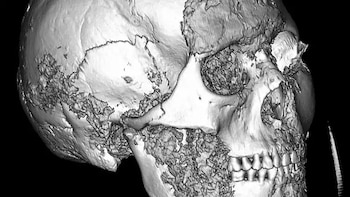

El caso surgió tras el estudio del cráneo de una mujer de la cultura pazyryk, hallada en el yacimiento de Verkh-Kaljin-2 en la meseta de Ukok, cerca de las fronteras actuales de China, Kazajistán y Mongolia. Allí, el análisis con tomografía computarizada reveló rastros de una intervención quirúrgica que, hasta ahora, no tenía precedentes en la literatura científica.

El equipo liderado por Vladímir Kaníguin utilizó un escáner Philips MX 16 para obtener 551 cortes digitales de alta resolución y crear un modelo 3D del cráneo.

“La tomografía permitió eliminar virtualmente los tejidos blandos momificados que ocultaban la estructura ósea”, explicó Kaníguin. De ese modo, los científicos accedieron a detalles anatómicos imposibles de observar a simple vista.

La tomografía mostró dos orificios artificiales en la zona dañada, de 1,5 milímetros de diámetro y dispuestos en ángulo recto. Alrededor de estos canales, el hueso presentaba signos de cicatrización, lo que indica que la paciente sobrevivió al procedimiento.

Además, en el interior de los canales se halló un material elástico, posiblemente tendón animal o crin de caballo, usado como una suerte de ligadura quirúrgica para estabilizar la mandíbula.